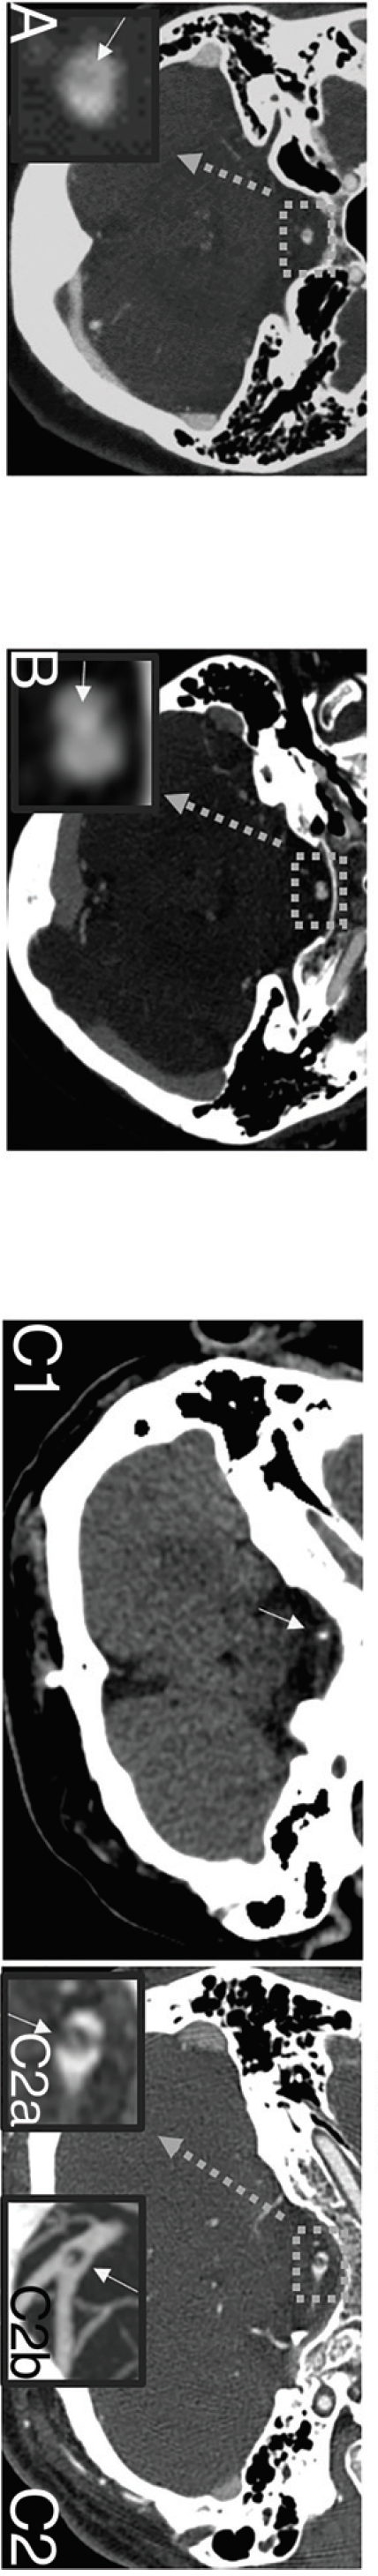

轴位CTA图像(A–C)和放大轴位CTA图像聚焦于不同患者的基底动脉开窗(A1、B1、C1)和后循环冠状位3D重建(A2、B2、C2),描绘了基底动脉开窗孔的不同形态:

2. 开窗伴钙化

3例基底动脉开窗的患者伴有钙化(3/59;5.1%)。其中一例患者的轴位CTA图像显示开窗(D,宽灰色箭头),其上方有一个小结节状钙化(E,细白色箭头),在冠状位MIP(F)和基底动脉3D重建(G)上更明显(粗灰色箭头为开窗,白色箭头为结节状钙化):